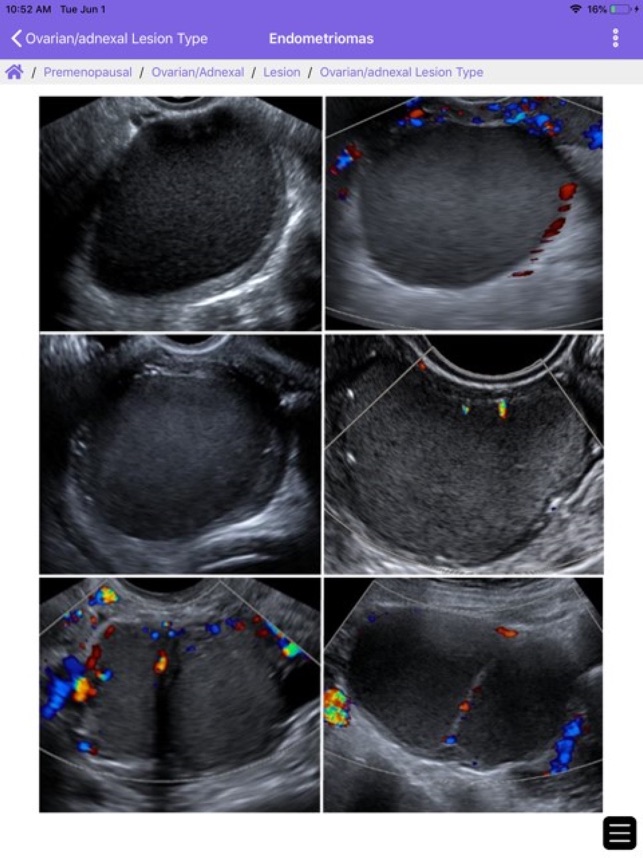

The ACR® Guidance App provides interactive mobile access to select clinical guidance content from the ACR website. Download to access the ACR Contrast Reaction Cards, Reporting and Data Systems (RADS), and Incidental Findings (IF) content. This app is intended for healthcare professionals such as radiologists, oncologists, referring physicians, and medical students who desire on the go reference materials from ACR. This app is not a medical device and should not be considered as one.ACR provides this mobile app for reference purposes only. It is not intended to substitute for the independent clinical judgment of a physician or other health care professional user. A physician or other user is solely responsible for verifying the currency and applicability of app content to a particular clinical situation and thus assumes all risk of use. As allowable under applicable law, ACR and ACR’s employees, officers, directors, agents, contractors and volunteers will not be liable for any damages